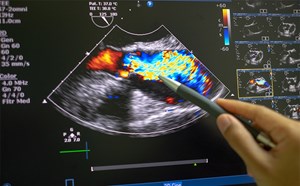

Cardiac